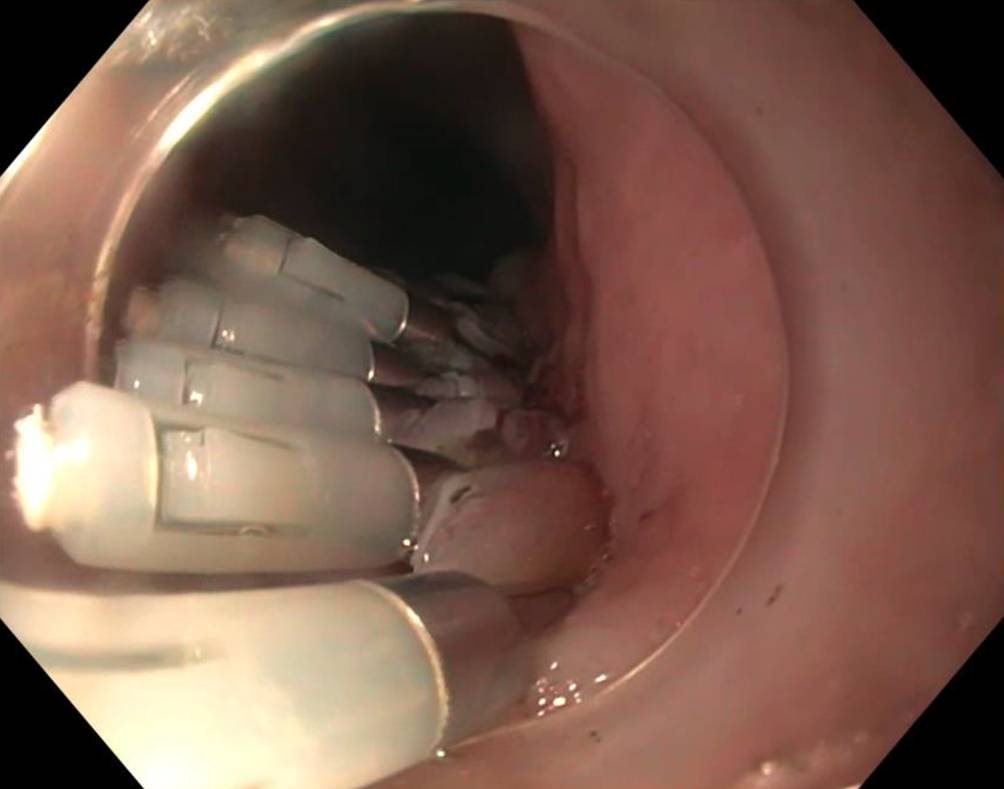

Wir führen POEM in Intubationsnarkose und mit CO2-Insufflation durch. Nach submuköser Injektion wird die Mukosa ca. 12 cm oberhalb der Kardia inzidiert und ein submuköser Tunnel über die Kardia hinweg bis in den proximalen Magen präpariert. Dann wird die innere Ringmuskulatur von 2 cm distal der Kardia nach proximal bis ca. 3 cm unterhalb der Mukosainzision durchtrennt, die Längsmuskulatur wird erhalten. Abschließend wird der Tunneleingang mit Clips verschlossen (Abb. 1, 2 und 3).

Abb. 3

Verschluss des Myotomie-Tunnels mit Clips